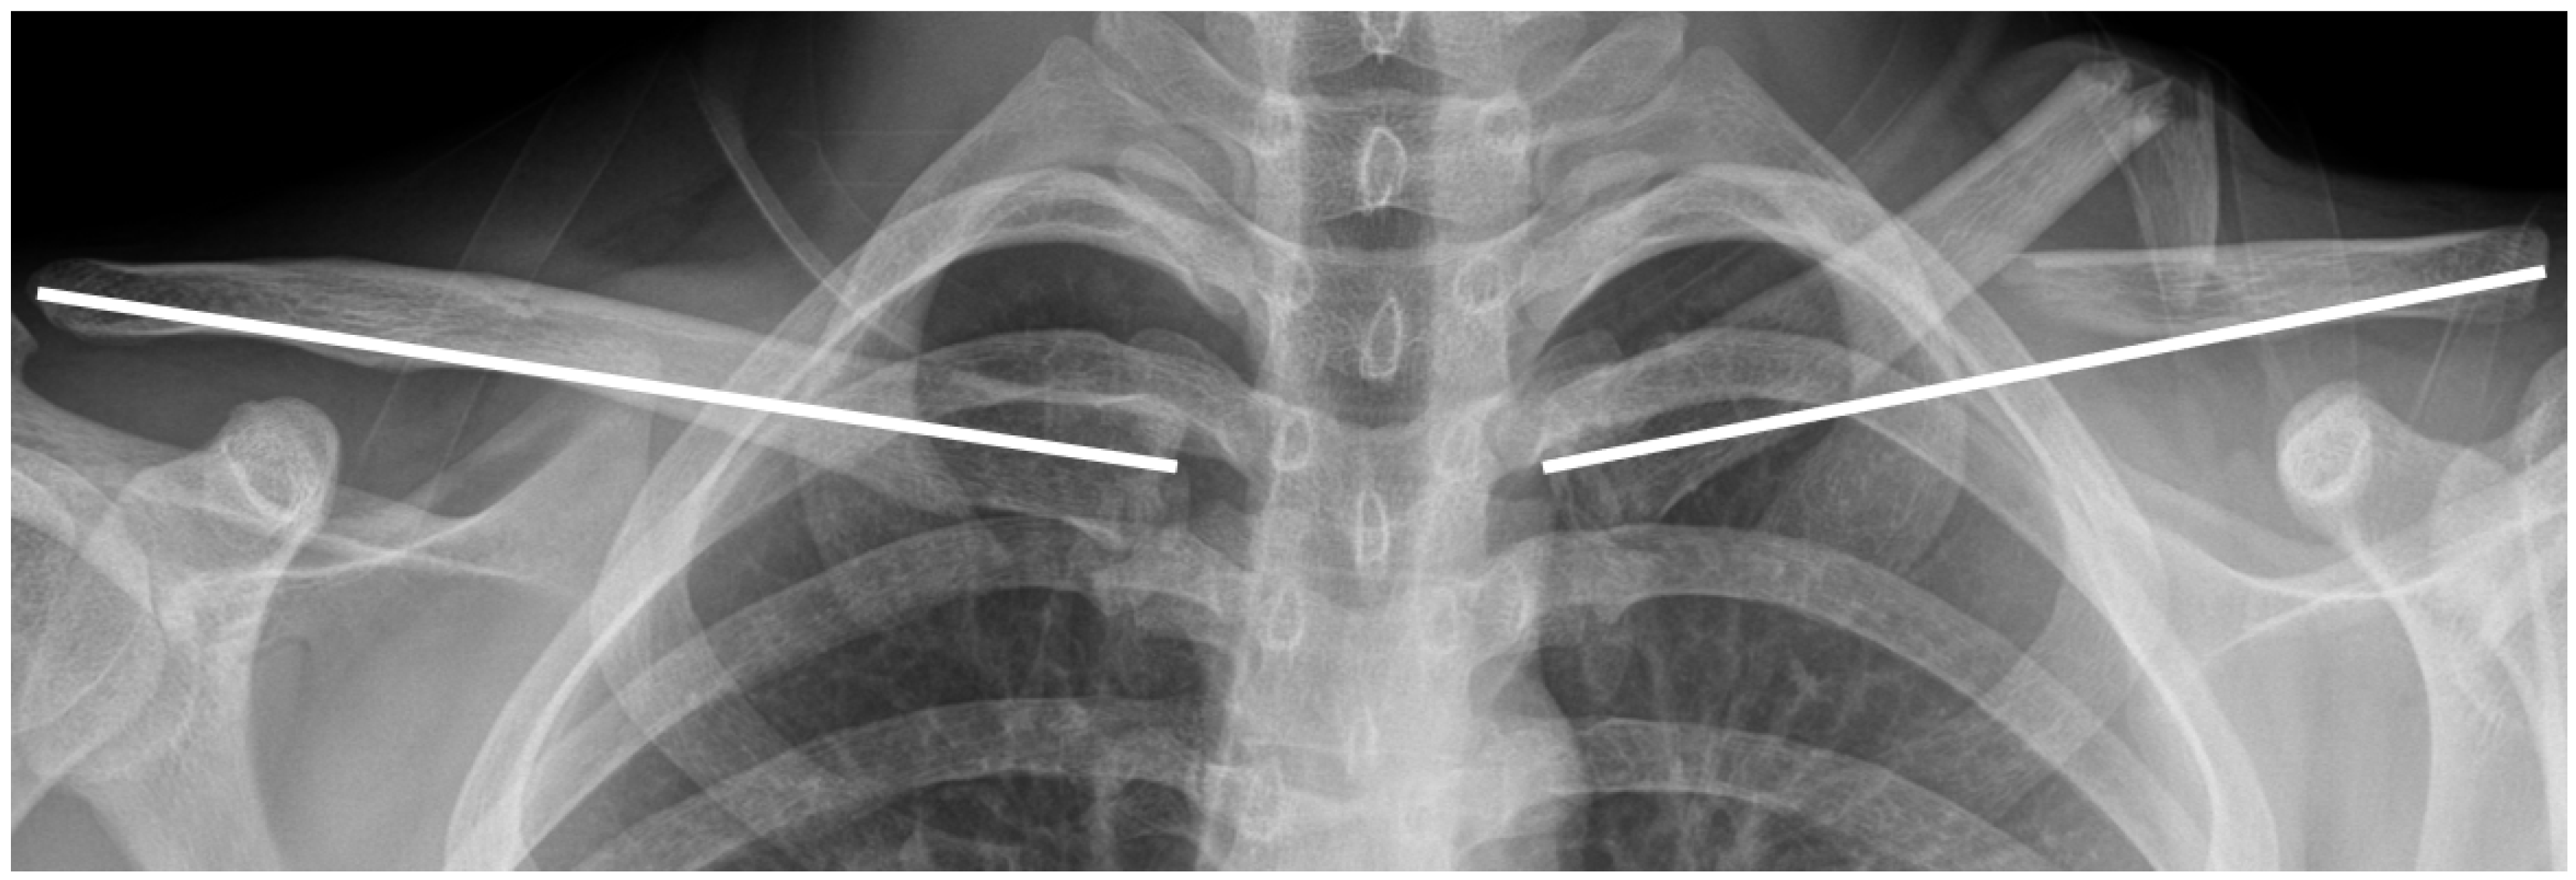

- Lima, G.V.; La Banca, V.; Murachovsky, J.; Nascimento, L.G.P.; Almeida, L.H.O.; Ikemoto, R.Y. Assessment of the measurement methods in midshaft clavicle fracture. BMC Musculoskelet. Disord. 2022, 23, 992. [Google Scholar] [CrossRef]